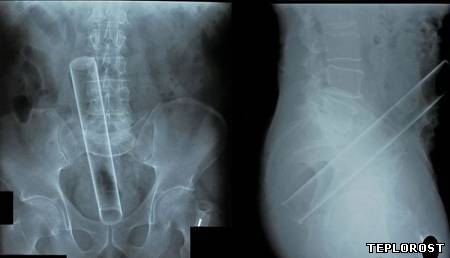

Застрявший в прямой кишке вибратор.